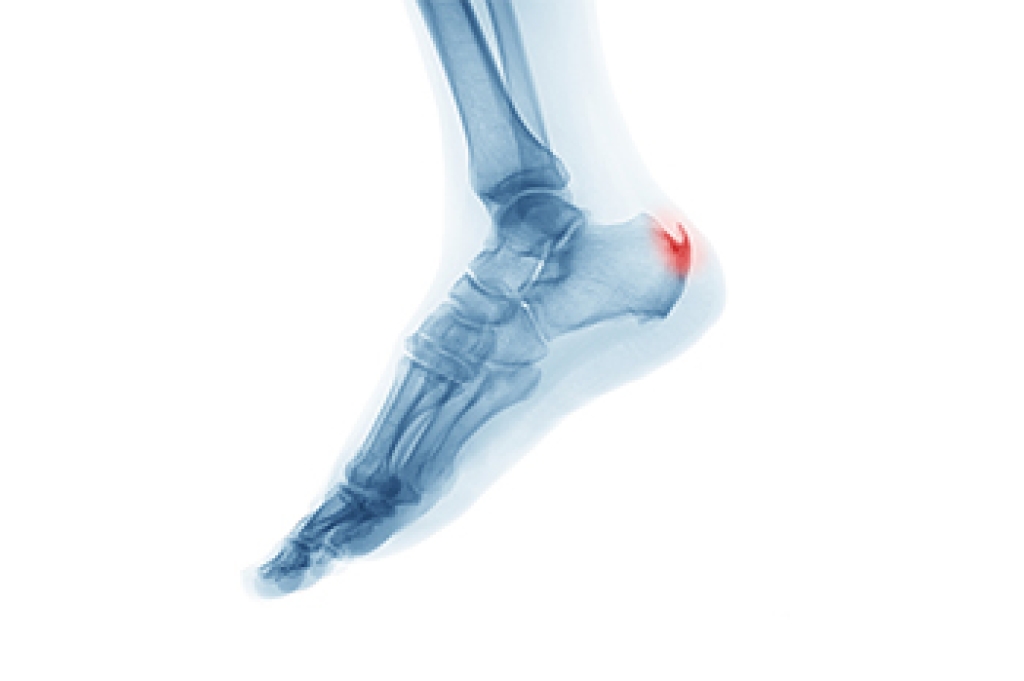

Sever’s disease is also known as calcaneal apophysitis, which is a medical condition that causes heel pain I none or both feet. The disease is known to affect children between the ages of 8 and 14.

Sever’s disease occurs when part of the child’s heel known as the growth plate (calcaneal epiphysis) is attached to the Achilles tendon. This area can suffer injury when the muscles and tendons of the growing foot do not keep pace with bone growth. Therefore, the constant pain which one experiences at the back of the heel will make the child unable to put any weight on the heel. The child is then forced to walk on their toes.